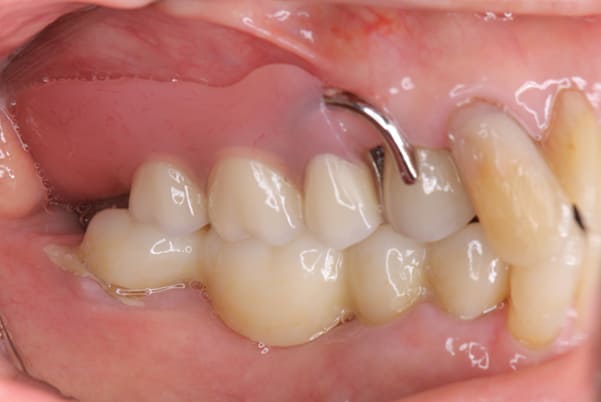

上あごに接する入れ歯に違和感がありになっていたとのことで、プラスチックが大きく削られた入れ歯をされていました。

そのため入れ歯の安定が悪く、お食事の際に入れ歯が動き、がたつきを感じられている状態でした。

前歯にバネにより見た目の問題も抱えておられました。

かみ合わせが低くなった歯を本来の高さに戻し、保険では使用できない歯に負担のかかりずらいバネで、歯の保存、審美性を確保しました。

前歯にバネを設定せず、見えない奥歯に維持力をもたせたバネを用い、またバネのかかる歯の負担軽減を目的に、被せ物は繋げることで強度を増す設計とすることで、入れ歯が動かずガタつき、審美性不良が解消されました。

入れ歯を修理する中で、入れ歯の上あごの接触面積ではなく、厚みに対しての違和感と診断し、薄い金属を用いた従来の厚みを1/3程度にした入れ歯にすることにより違和感は消失しました。